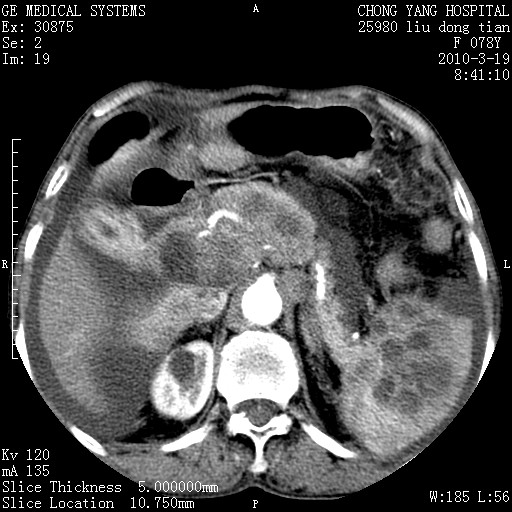

标题: CT25199:F 78Y 腹胀半年 消瘦乏力 [打印本页]

胆囊壁增厚并明显强化,胆囊癌伴多发转移瘤可能性大,淋巴瘤不除外,右肾囊肿,胸腹水.

考虑nhl,肝、脾、腹膜腔及腹膜后多发淋巴结受侵,腹水,右肾囊肿,慢性胆囊炎,右侧少量胸腔积液。

胰头有肿块形成,胰头ca伴肝脾、腹膜腹膜后转移

胆囊有软组织影有强化,支持胆囊癌,肝脾、腹膜后淋巴结转移。

nhl的淋巴结多围绕主动脉,而且主动脉会移位,所以不考虑nhl。

分开来讲:肝左叶、尾叶病灶有不均强化像肝癌;

脾脏病灶无强化,像多发囊肿或淋巴管瘤,不除外淋巴瘤(低强化);

胆囊增生性病变:胆囊癌,腺肌增生症,慢性胆囊炎;

肝门、胰腺头、腹膜后多个团块: 淋巴瘤,转移;

腔静脉肝内段细小有无布加可能?

一元论最好了 淋巴瘤所致改变; 胆囊癌转移不像,胆囊周围肝组织清晰,肝癌淋巴结转移?三元论都不止。

胰头ca伴肝脾、腹膜腹膜后转移!

最后报的胰头癌多发转移,脾脏单独考虑囊肿或淋巴管瘤。